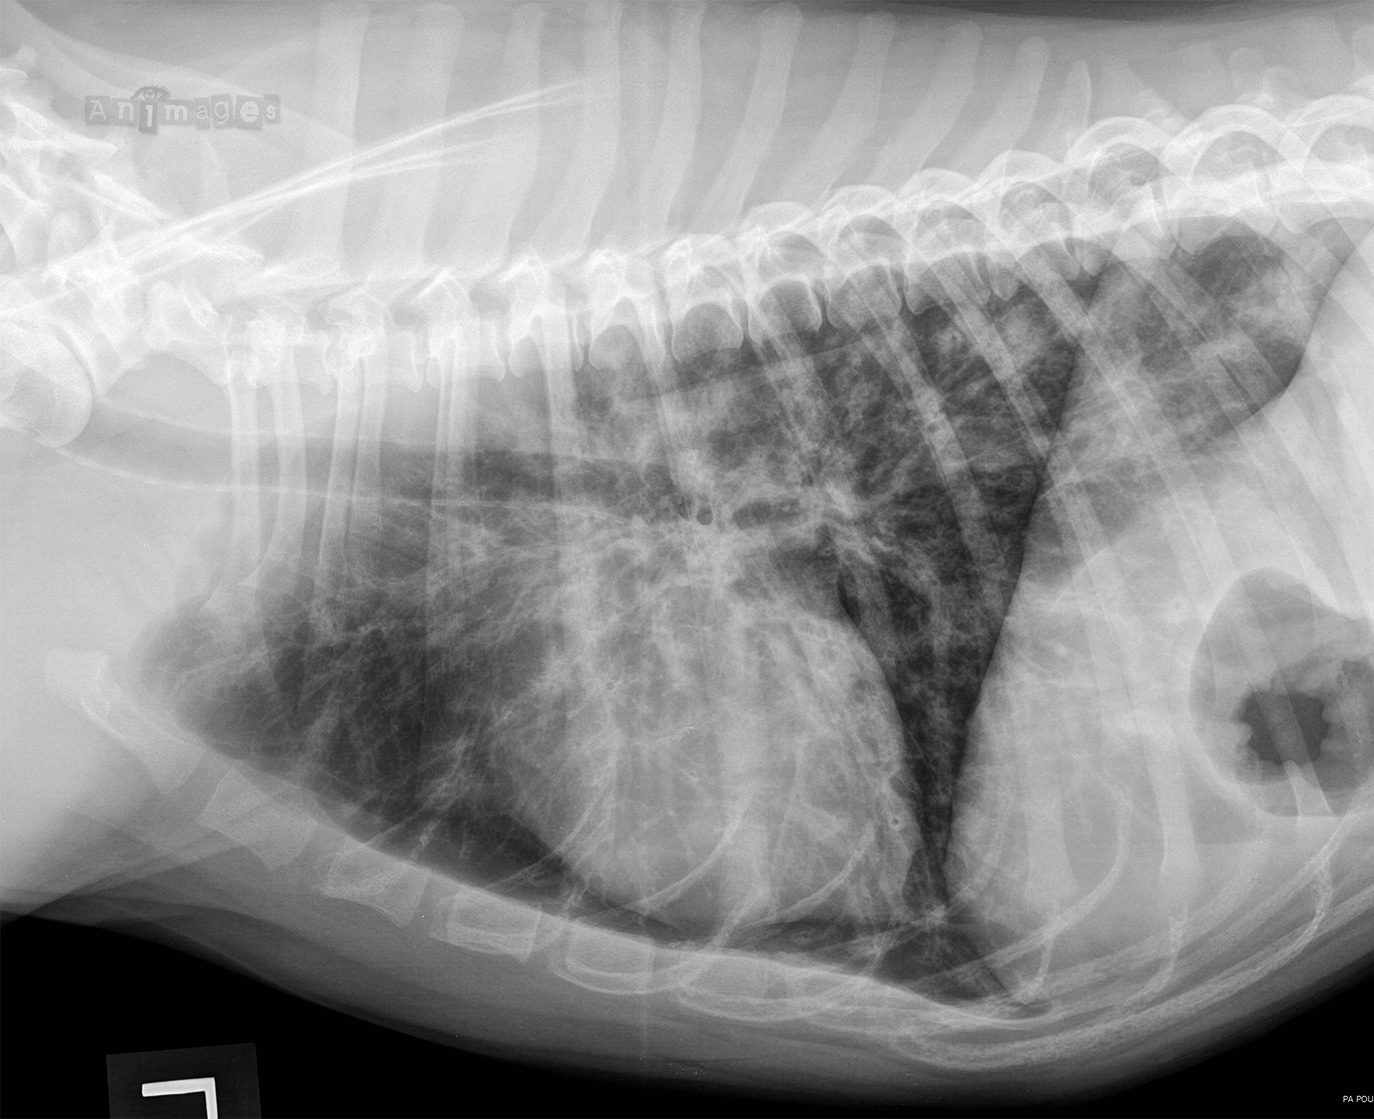

Lateral G J1

Latérale gauche